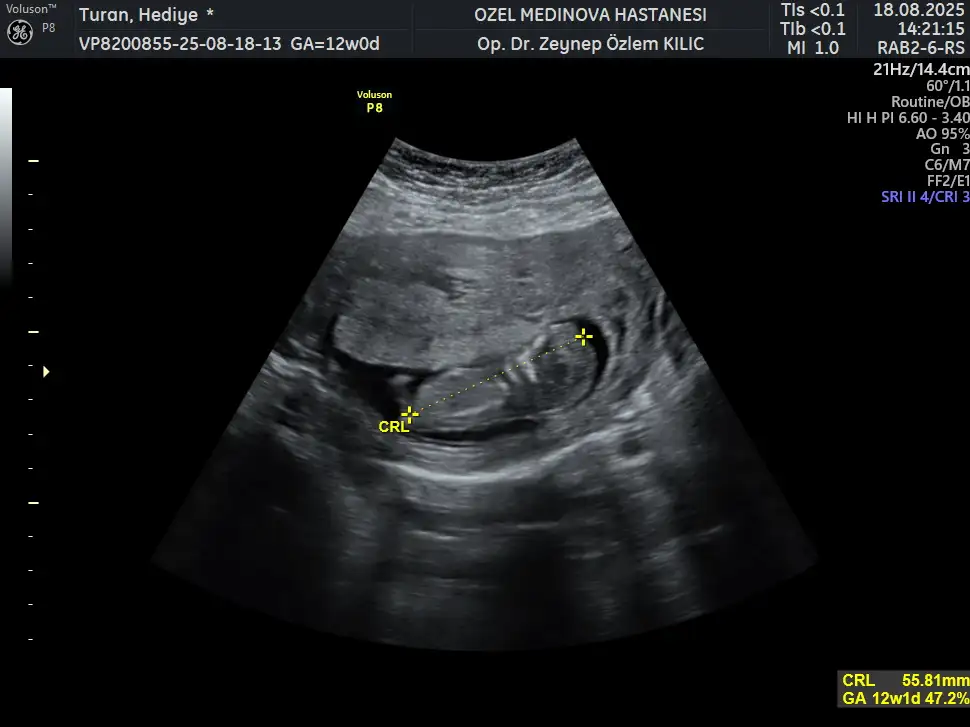

Benim nedir sizce 12+1Erkek bence

MerhabalarBenim nedir sizce 12+1

Oncelikle saglikli gelsin bebeginiz

Doktor cinsiyyet tahmininde bulunmadi mi acaba? Cunki 12+1 . Genelde soylemeyince bu haftalarda kiz geliyor. Erkegi hemen gore biliyorlarmis

Doktor olarak devlete gidiyorum ve 4 aylık olunca dedi bende bu geçtiğimiz pazartesi özele gitim ikili test için ve doktor net olarak söylemesede kız bebek gibi duruyor dedi artık birdahaki kontrole net söyler çünkü 15+3olurum kesin net olarak söyler ama ben meraktan çatlarım yaaa

13. haftadan sonraki bir ultrason fotoğrafı varsa chatgptye sorun bence nub teorisine göre benimkini ve arkadaşımın bebeğini doğru tahmin ettiBenim nedir sizce 12+1